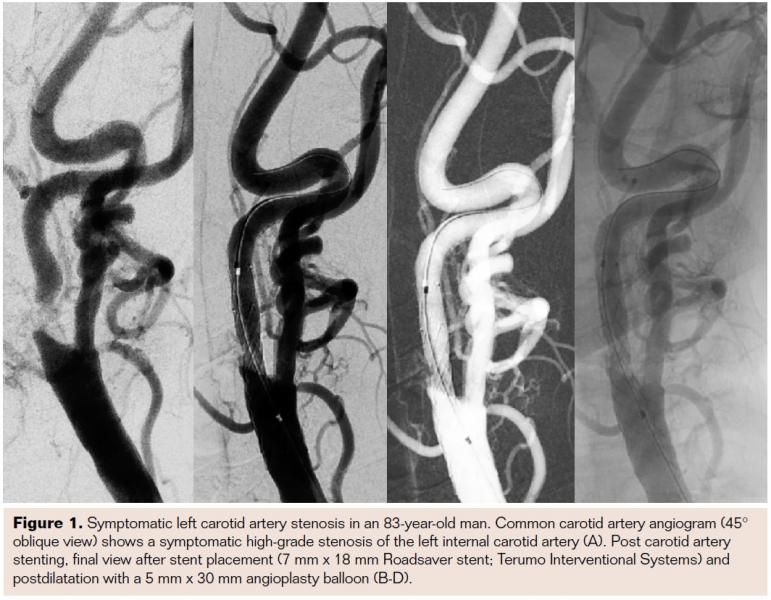

In addition to these first clinical data and experience with the Roadsaver stent, it is necessary to clarify that a certain learning curve for safe and accurate stent placement is warranted. This is because experience is needed to predict the stent length. It is highly recommended to start with larger diameters or longer stent lengths in order to achieve good lesion covering. In Figures 1-3 the Roadsaver stent is shown in 3 different anatomical locations.

The device is compatible with a 5 Fr sheath or 6 Fr guiding catheter. Up to the point of 50% deployment, the push-and-pull stent delivery system is full resheathable and repositionable. The low profile (5 Fr) enhances the crossability for primary stenting. The double-layer micromesh scaffold should enable sustained embolic protection by tight plaque coverage. The feasibility, efficacy, and safety of performing carotid angioplasty and stenting with the Roadsaver stent has been demonstrated in two studies.15,16 Kedev et al used transradial slender 5 Fr techniques to implant the Roadsaver stent in the left and right carotid arteries with promising results.16

The Roadsaver stent (Terumo Interventional Systems) currently is the only FDA-approved, CE-marked, commercially available double-layer micromesh stent. This self-tapering stent is composed of two nitinol (nickel titanium) interwoven mesh layers, creating a flexible scaffold. The inner mesh has an extremely small cell size (0.381 mm2), which is designed to prevent release of emboli. The internal fine meshwork should prevent plaque prolapse.17 A number of micromesh cells fit into one macromesh cell, acting like a metallic covered stent.